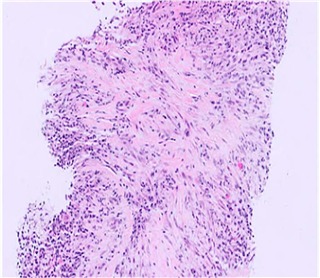

いくつかの重要な顕微鏡的特徴は、影響を受けた臓器全体で一貫して特定されています。最も特徴的な所見の1つは、組織内の多数のリンパ球とポリクローナル形質細胞からなる高密度のリンパ形質細胞浸潤です。この浸潤は、疾患の慢性炎症性を反映しており、通常、関与するすべての部位で顕著です。分類基準では、組織病理学的診断の確定的な診断には、通常、リンパ形質細胞浸潤、花むしろ様線維化、閉塞性静脈炎の3つの主要な特徴のうち少なくとも2つが存在すること、およびIgG4陽性形質細胞の明らかな増加とIgG4陽性形質細胞/IgG陽性形質細胞比上昇(>40%)が必要であることを強調しています。診断の複雑さと他の状態と重複する可能性を考慮すると、治療を開始する前に生検を施行することが強く推奨されます。

IgG4関連疾患の主な組織病理学的特徴 (文献 1)より)

| 組織学的所見 | 特徴 | 組織学的顕微鏡写真 |

|---|---|---|

| 高密度リンパ形質細胞浸潤 | IgG4関連疾患に特徴的な線維症を伴う緻密なリンパ形質細胞浸潤 (HE染色、×400)。 |

|

| 花むしろ様線維症(Storiform Fibrosis) | リンパ形質細胞性炎症が散在する紡錘体細胞とコラーゲン束の花むしろ様配置。このパターンでは、線維化組織は、側転のスポークに似た、炎症病巣の周囲に放射状に広がる渦巻き状または渦巻き状に配置されます。この独特の線維構造は、この疾患の特徴として広く見なされており、その組織学的認識に大きく貢献しています。 (HE染色、×100) |